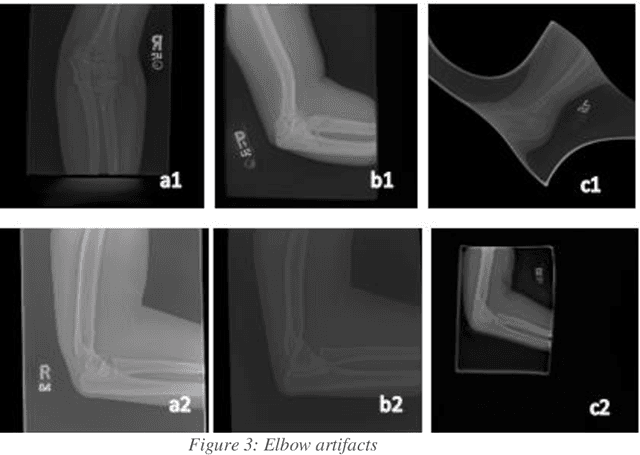

Abstract:In medical imaging, access to data is commonly limited due to patient privacy restrictions and the issue that it can be difficult to acquire enough data in the case of rare diseases.[1] The purpose of this investigation was to develop a reusable open-source synthetic image generation pipeline, the GAN Image Synthesis Tool (GIST), that is easy to use as well as easy to deploy. The pipeline helps to improve and standardize AI algorithms in the digital health space by generating high quality synthetic image data that is not linked to specific patients. Its image generation capabilities include the ability to generate imaging of pathologies or injuries with low incidence rates. This improvement of digital health AI algorithms could improve diagnostic accuracy, aid in patient care, decrease medicolegal claims, and ultimately decrease the overall cost of healthcare. The pipeline builds on existing Generative Adversarial Networks (GANs) algorithms, and preprocessing and evaluation steps were included for completeness. For this work, we focused on ensuring the pipeline supports radiography, with a focus on synthetic knee and elbow x-ray images. In designing the pipeline, we evaluated the performance of current GAN architectures, studying the performance on available x-ray data. We show that the pipeline is capable of generating high quality and clinically relevant images based on a lay person's evaluation and the Fr\'echet Inception Distance (FID) metric.